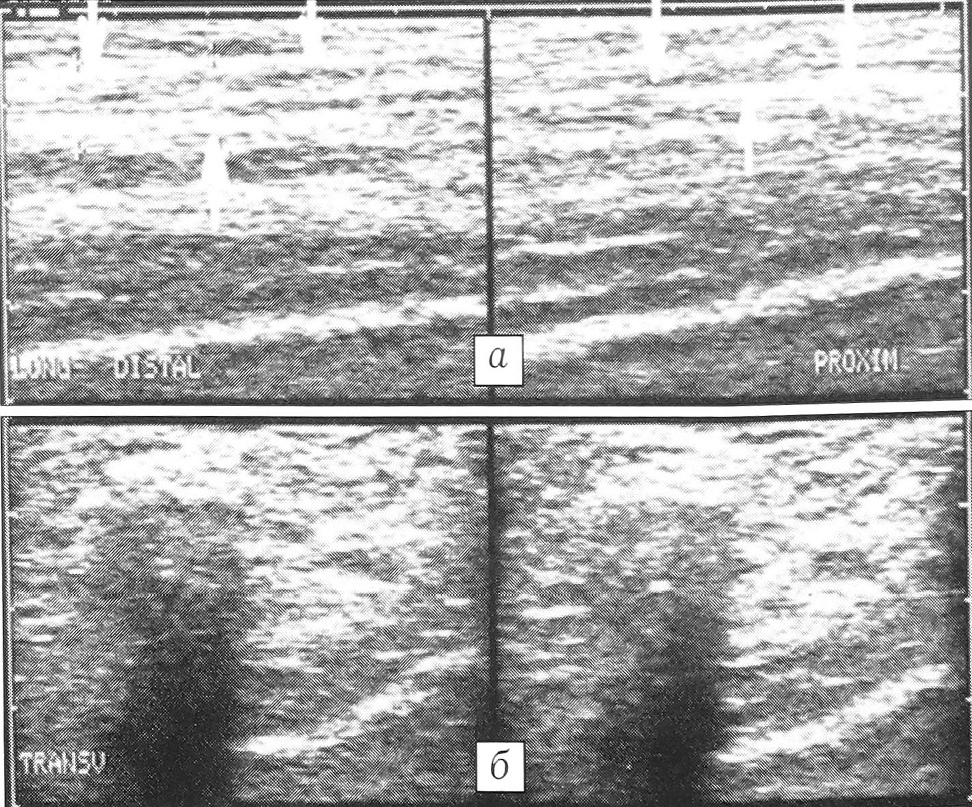

При продольном ультразвуковом сканировании фиброзно-хрящевой тяж визуализировался как лентовидное образование, в большинстве случаев с определяемыми контурами, при поперечном сканировании имел овальную, округлую или неправильную форму (рис. 1). Толщина тяжа, составлявшая обычно 3~6 мм, увеличивалась в дистальном направлении. Ультразвуковое исследование позволяло проследить протяженность тяжа, неоднородность его структуры. У части пациентов проследить данное образование в проксимальном направлении удавалось лишь до середины голени, далее контуры его становились нечеткими, а эхоплотность — одинаковой с окружающими тканями. При функциональной сонографии выявляли возможность смещения фиброзно-хрящевого тяжа при тыльной и подошвенной флексии.

Рис. 1. Ультрасонографическое изображение фибрознохрящевого малоберцового тяжа: а — при продольном направлении сканирования, б — при поперечном.